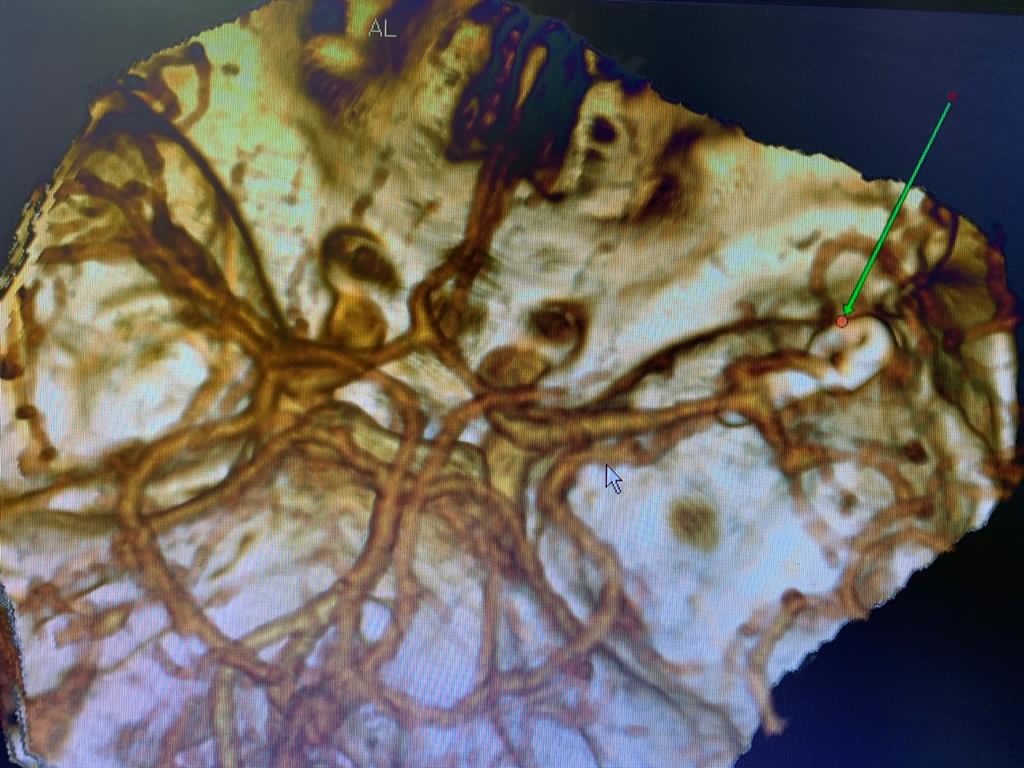

После проведённого обследования был поставлен диагноз: разорвавшаяся мешотчатая аневризма средней мозговой артерии. Опасностью при этом заболевании является высокий риск повторного кровоизлияния, что может привести к летальному исходу.

Послеоперационный контроль- аневризма выключена из кровотока полностью, все сосуды проходимы.